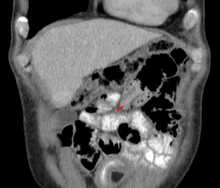

| An intussuception as seen on CT | |

An intussusception is a medical condition in which a part of the intestine invaginates (folds into) into another section of intestine, similar to the way the parts of a collapsible telescope retract into one another.[1] This can often result in an obstruction. The part that prolapses into the other is called the intussusceptum, and the part that receives it is called the intussuscepiens. Intussusception is a medical emergency and a patient should be seen immediately to reduce risk.

An intussusception is often suspected based on history and physical exam, including observation of Dance's sign. A digital rectal examination is particularly helpful in children, as part of the intussusceptum may be felt by the finger. A definite diagnosis often requires confirmation by diagnostic imaging modalities. Ultrasound is the imaging modality of choice for diagnosis and exclusion of intussusception, due to its high accuracy and lack of radiation. The appearance of target sign (also called "doughnut sign" on a sonograph, usually around 3 cm in diameter, confirms the diagnosis. The image seen on transverse sonography or computed tomography is that of a doughnut shape, created by the hyperechoic central core of bowel and mesentery surrounded by the hypoechoic outer edematous bowel.[7] In longitudinal imaging, intussusception resembles a sandwich.[7]